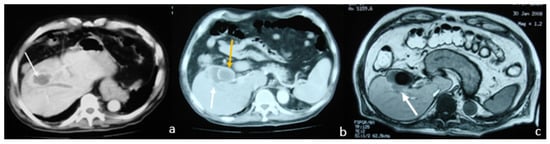

2.2. Case 2